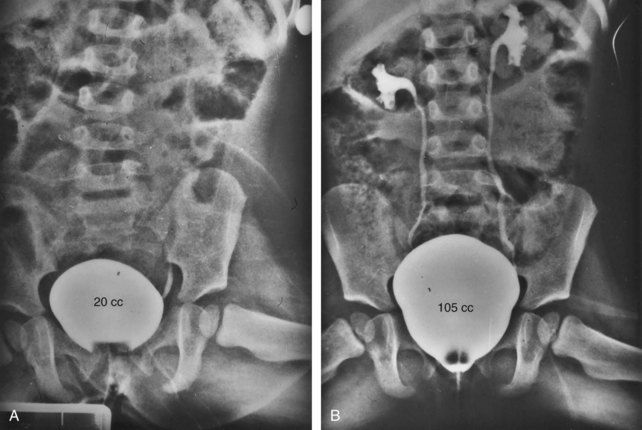

In a study by Gearhart and colleagues (1993c), 13 adult men born with bladder exstrophy were evaluated with MRI of the pelvis to evaluate the size and configuration of the prostate and sex accessory organs. The volume, weight, and maximum cross-sectional area of the prostate appeared normal compared with published control values (Fig. 124–8). However, in none of the patients did the prostate extend circumferentially around the urethra, and the urethra was anterior to the prostate in all patients. Except for studies to document the presence of the prostate gland or its size, data do not exist concerning the function of the prostate gland in the patient with exstrophy. Silver and colleagues (1997a) reported free and total prostate-specific antigen levels for a group of adult men with bladder exstrophy. Although they were measurable, they were below the upper limits of established age-specific reference ranges for normal men. The vas deferens and ejaculatory ducts are normal in the exstrophy patient, provided they are not injured iatrogenically. Also, the mean seminal vesicle length in men with exstrophy was normal compared with published controls. Additional evaluation of the puborectalis muscle group was undertaken, and these muscles were found to be widely separated and provided lateral support of the prostate with a narrower puborectalis angle in those who were continent and had undergone prior iliac osteotomy.

Figure 124–8 A, Axial T2-weighted image of the midprostate in a 20-year-old continent patient with bladder exstrophy. Small arrowhead, lumen of the urethra; medium arrowhead, transitional zone; large arrowhead, peripheral zone. Curved arrow, fibrous band of the intersymphyseal bar. B, Sagittal T2-weighted image through the midprostate gland shows anterior urethra (double arrows) and posterior prostate gland. Intersymphyseal fibrous band (curved arrow) extends along the entire length of the prostate.